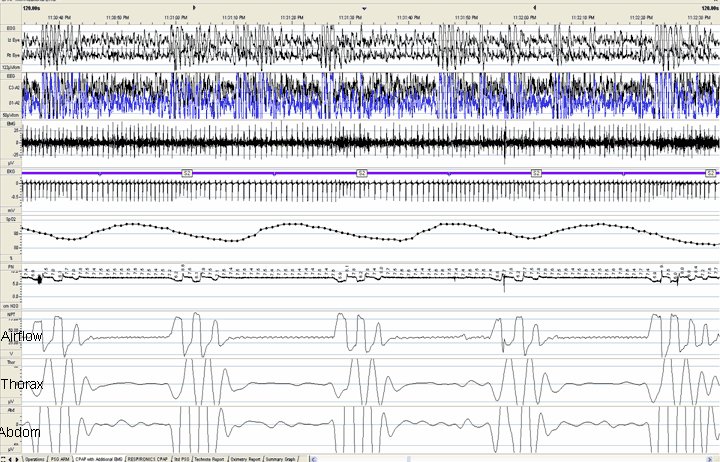

The fragment below is a 2 minute recording from a CPAP titration study. What respiratory events are shown on the recording?

The respiratory events observed in this fragment are apneas. There are features that are suggestive of a central apnea (i.e. cardiac oscillations in the airflow channel). There are also features suggestive of an obstructive apnea (i.e. persistent respiratory effort, particularly in the abdominal effort channel). Review of the study by the sleep physician revealed that the effort channels were filtered inappropriately. The low frequency filter was set at 0.1 Hz and the high frequency filter was set at 0.5 Hz. When the high frequency filters was increased to 15Hz, the fragment appears as in the Figure.

In this appropriately filtered fragment, cardiac oscillations are now apparent in both the thoracic and abdominal effort signals. The lack of increasing thoraco-abdominal movements or paradox effort during the apnea confirms the presence of a central apnea.